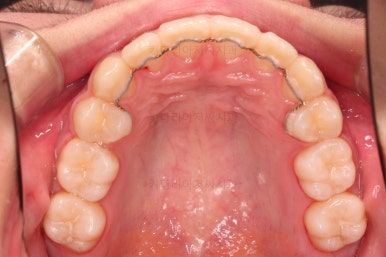

우선 윗니만 장치를 부착했습니다.

순서는 윗니 장치 부착 후 발치를 하고, 가지런하게 된 뒤에, 과개교합 개선을 위한 특별한 장치가 들어가면서 아랫니에도 브라켓을 부착하기로 정했습니다.

이번 환자분이 선택한 장치는 엠파워 메탈이라고 하는 자가결찰 금속 브라켓입니다.

메탈 브라켓이라고 다 구식의 안좋은 장치가 아닙니다.

"자가결찰" 브라켓이면 모두 우수한 성능의 장치인데요.

철사를 잡아주는(결찰) 캡이 브라켓에 달려 있어 스스로 묶을 수 있는(자가) 브라켓입니다.

즉, 세라믹 중에서도 자가결찰인 것이 있고 아닌 것이 있으며, 메탈 중에서도 자가결찰인 것이 있고 아닌 것이 있습니다.

윗니가 가지런해진 뒤에는 부산치아교정치과 키다리아저씨치과에서는 ABP라고 하는 장치를 사용해 주면서 아랫니에도 브라켓을 부착합니다.

깊게 물리는 과개교합을 개선하기 위함인데요.

과개교합을 개선하기 위해서는 미니스크류를 사용하기도 하고 ABP를 사용하기도 하며, 윗니 앞니를 코 방향으로 밀어넣기도 합니다.